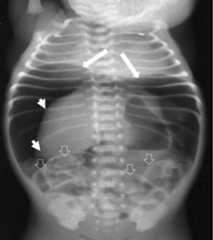

Pneumoperitoneum

Pneumoperitoneum:

Big white arrows show air under the diaphragm leading to its elevation. Small white arrows delineate the inferiorly displaced liver border. Empty arrows show Rigler sign.